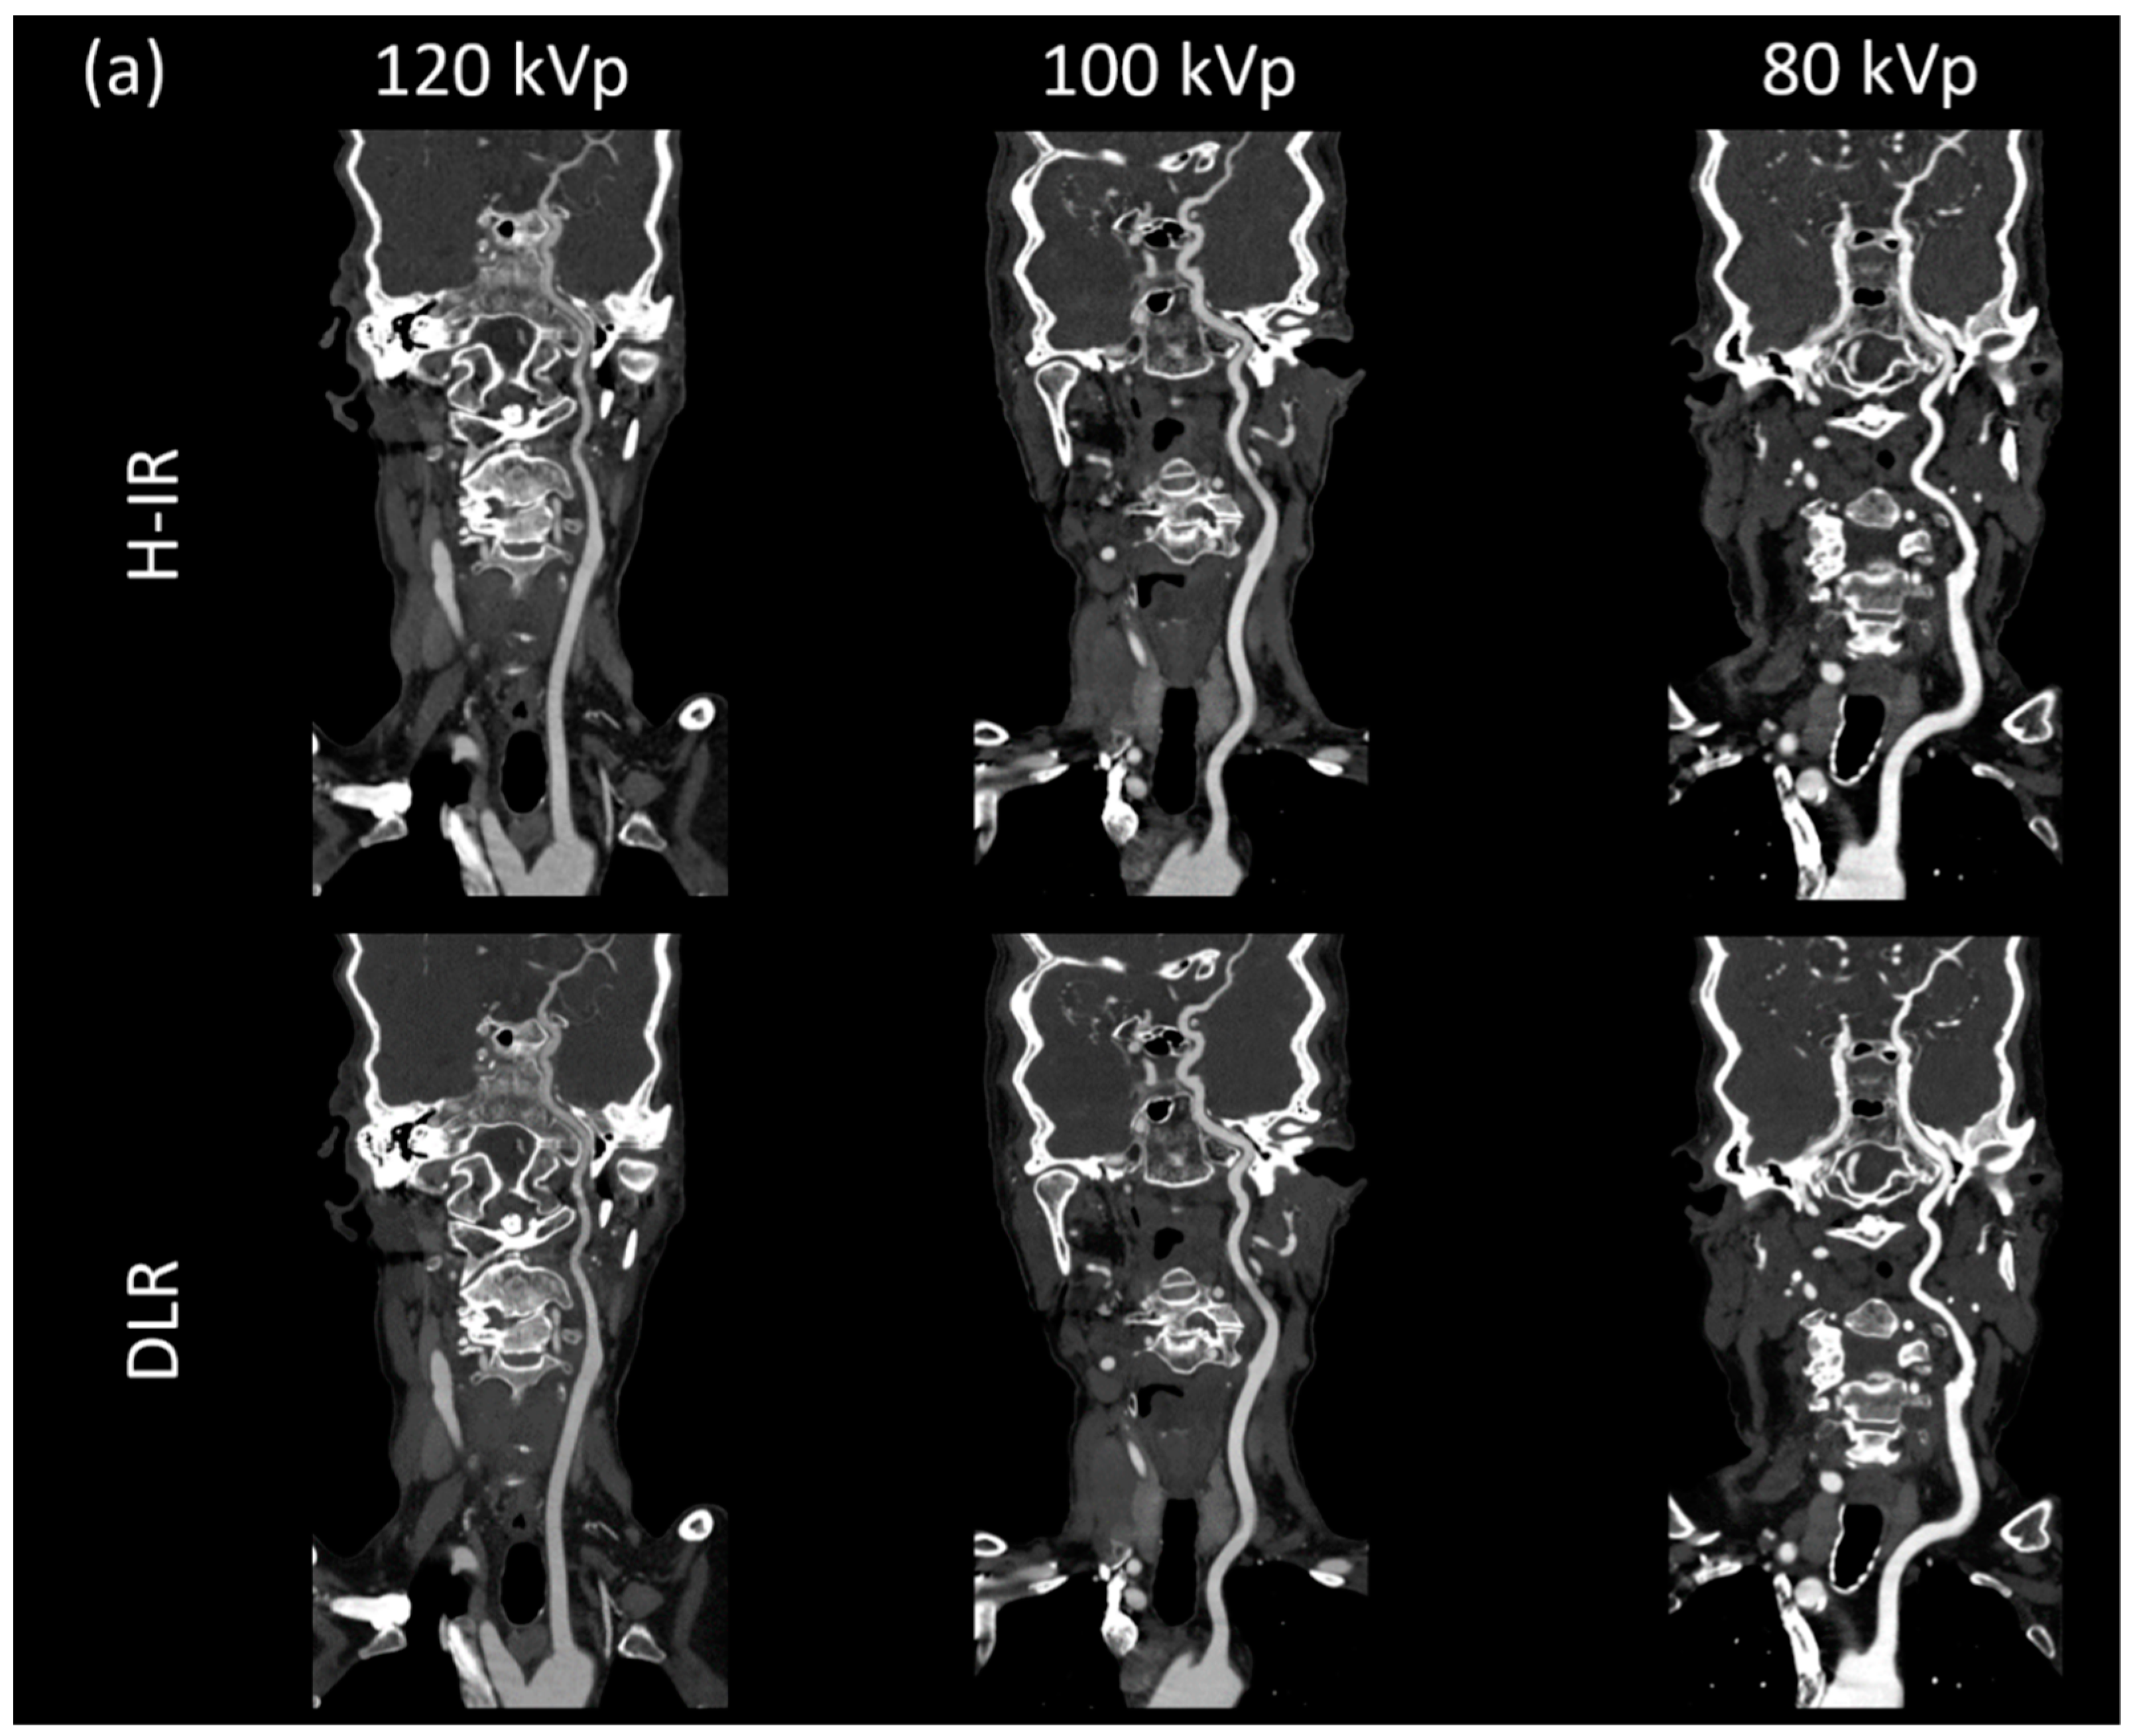

3.3.1. Image Signal Fluctuation with DLR vs. H-IR

3.3.2. Comparison of the Two Reconstruction Techniques at Constant kVp Value

3.3.3. Comparison of Low kVp plus DLR vs. Standard kVp plus DLR

3.3.4. Comparison of Low kVp plus DLR vs. Standard kVp plus H-IR

3.4. Qualitative Image Analysis